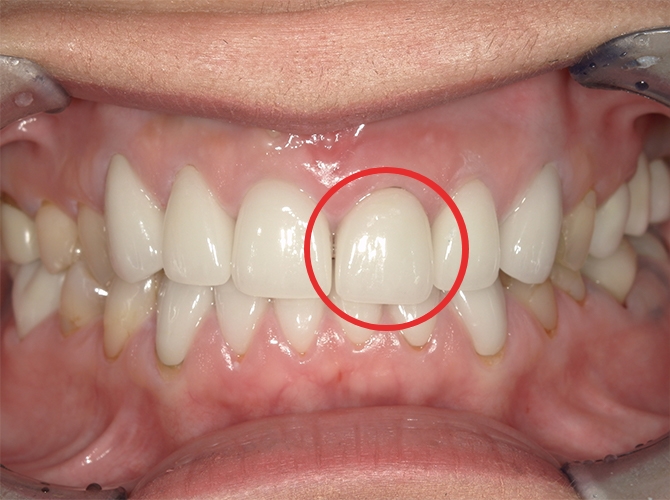

手術を終えて

笑った時に自然な口元になりたいという思いでお願いしました。母が「何とかなりませんか?」と相談した際も「治療期間が長くなるけれど、時間をかけてでも綺麗な仕上がりになるようなんとかします」と私に合った方法を考えてくれました。

先生から一言

術後、泣いて喜んでくださったのを覚えています。笑った時のスマイルラインも自然で、人工歯には思えません。天然歯かインプラントか、歯医者さんが見ても分からないと思います。